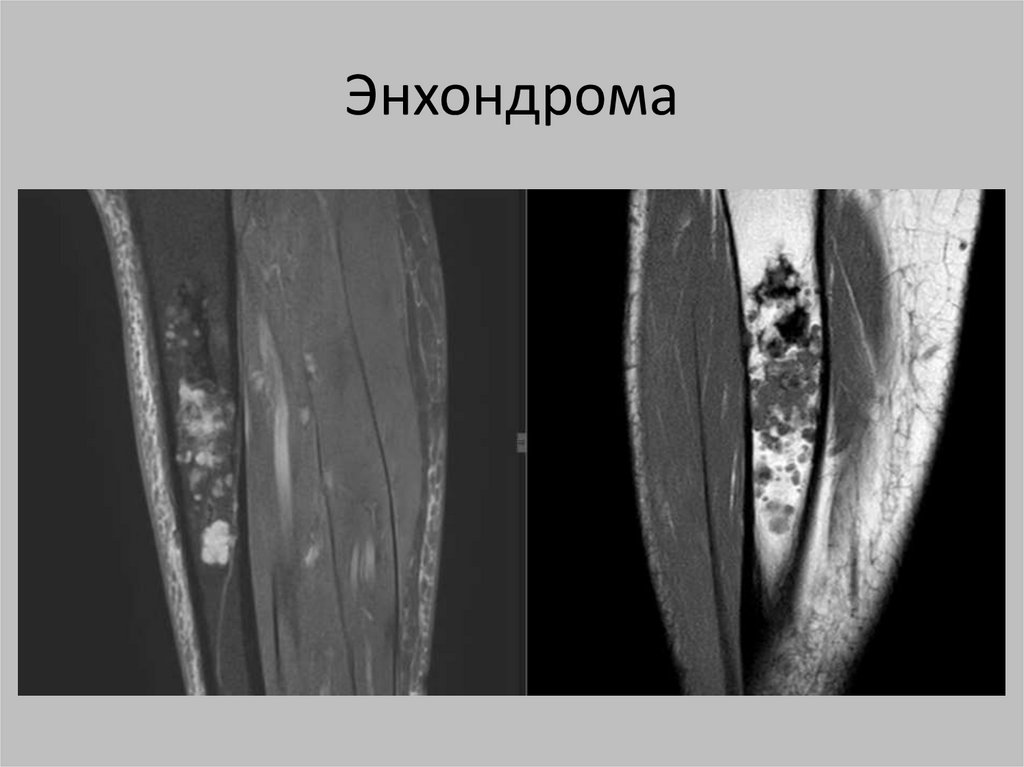

Энхондрома